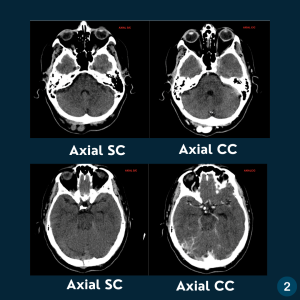

Caso do dia – Sinus Pericranii